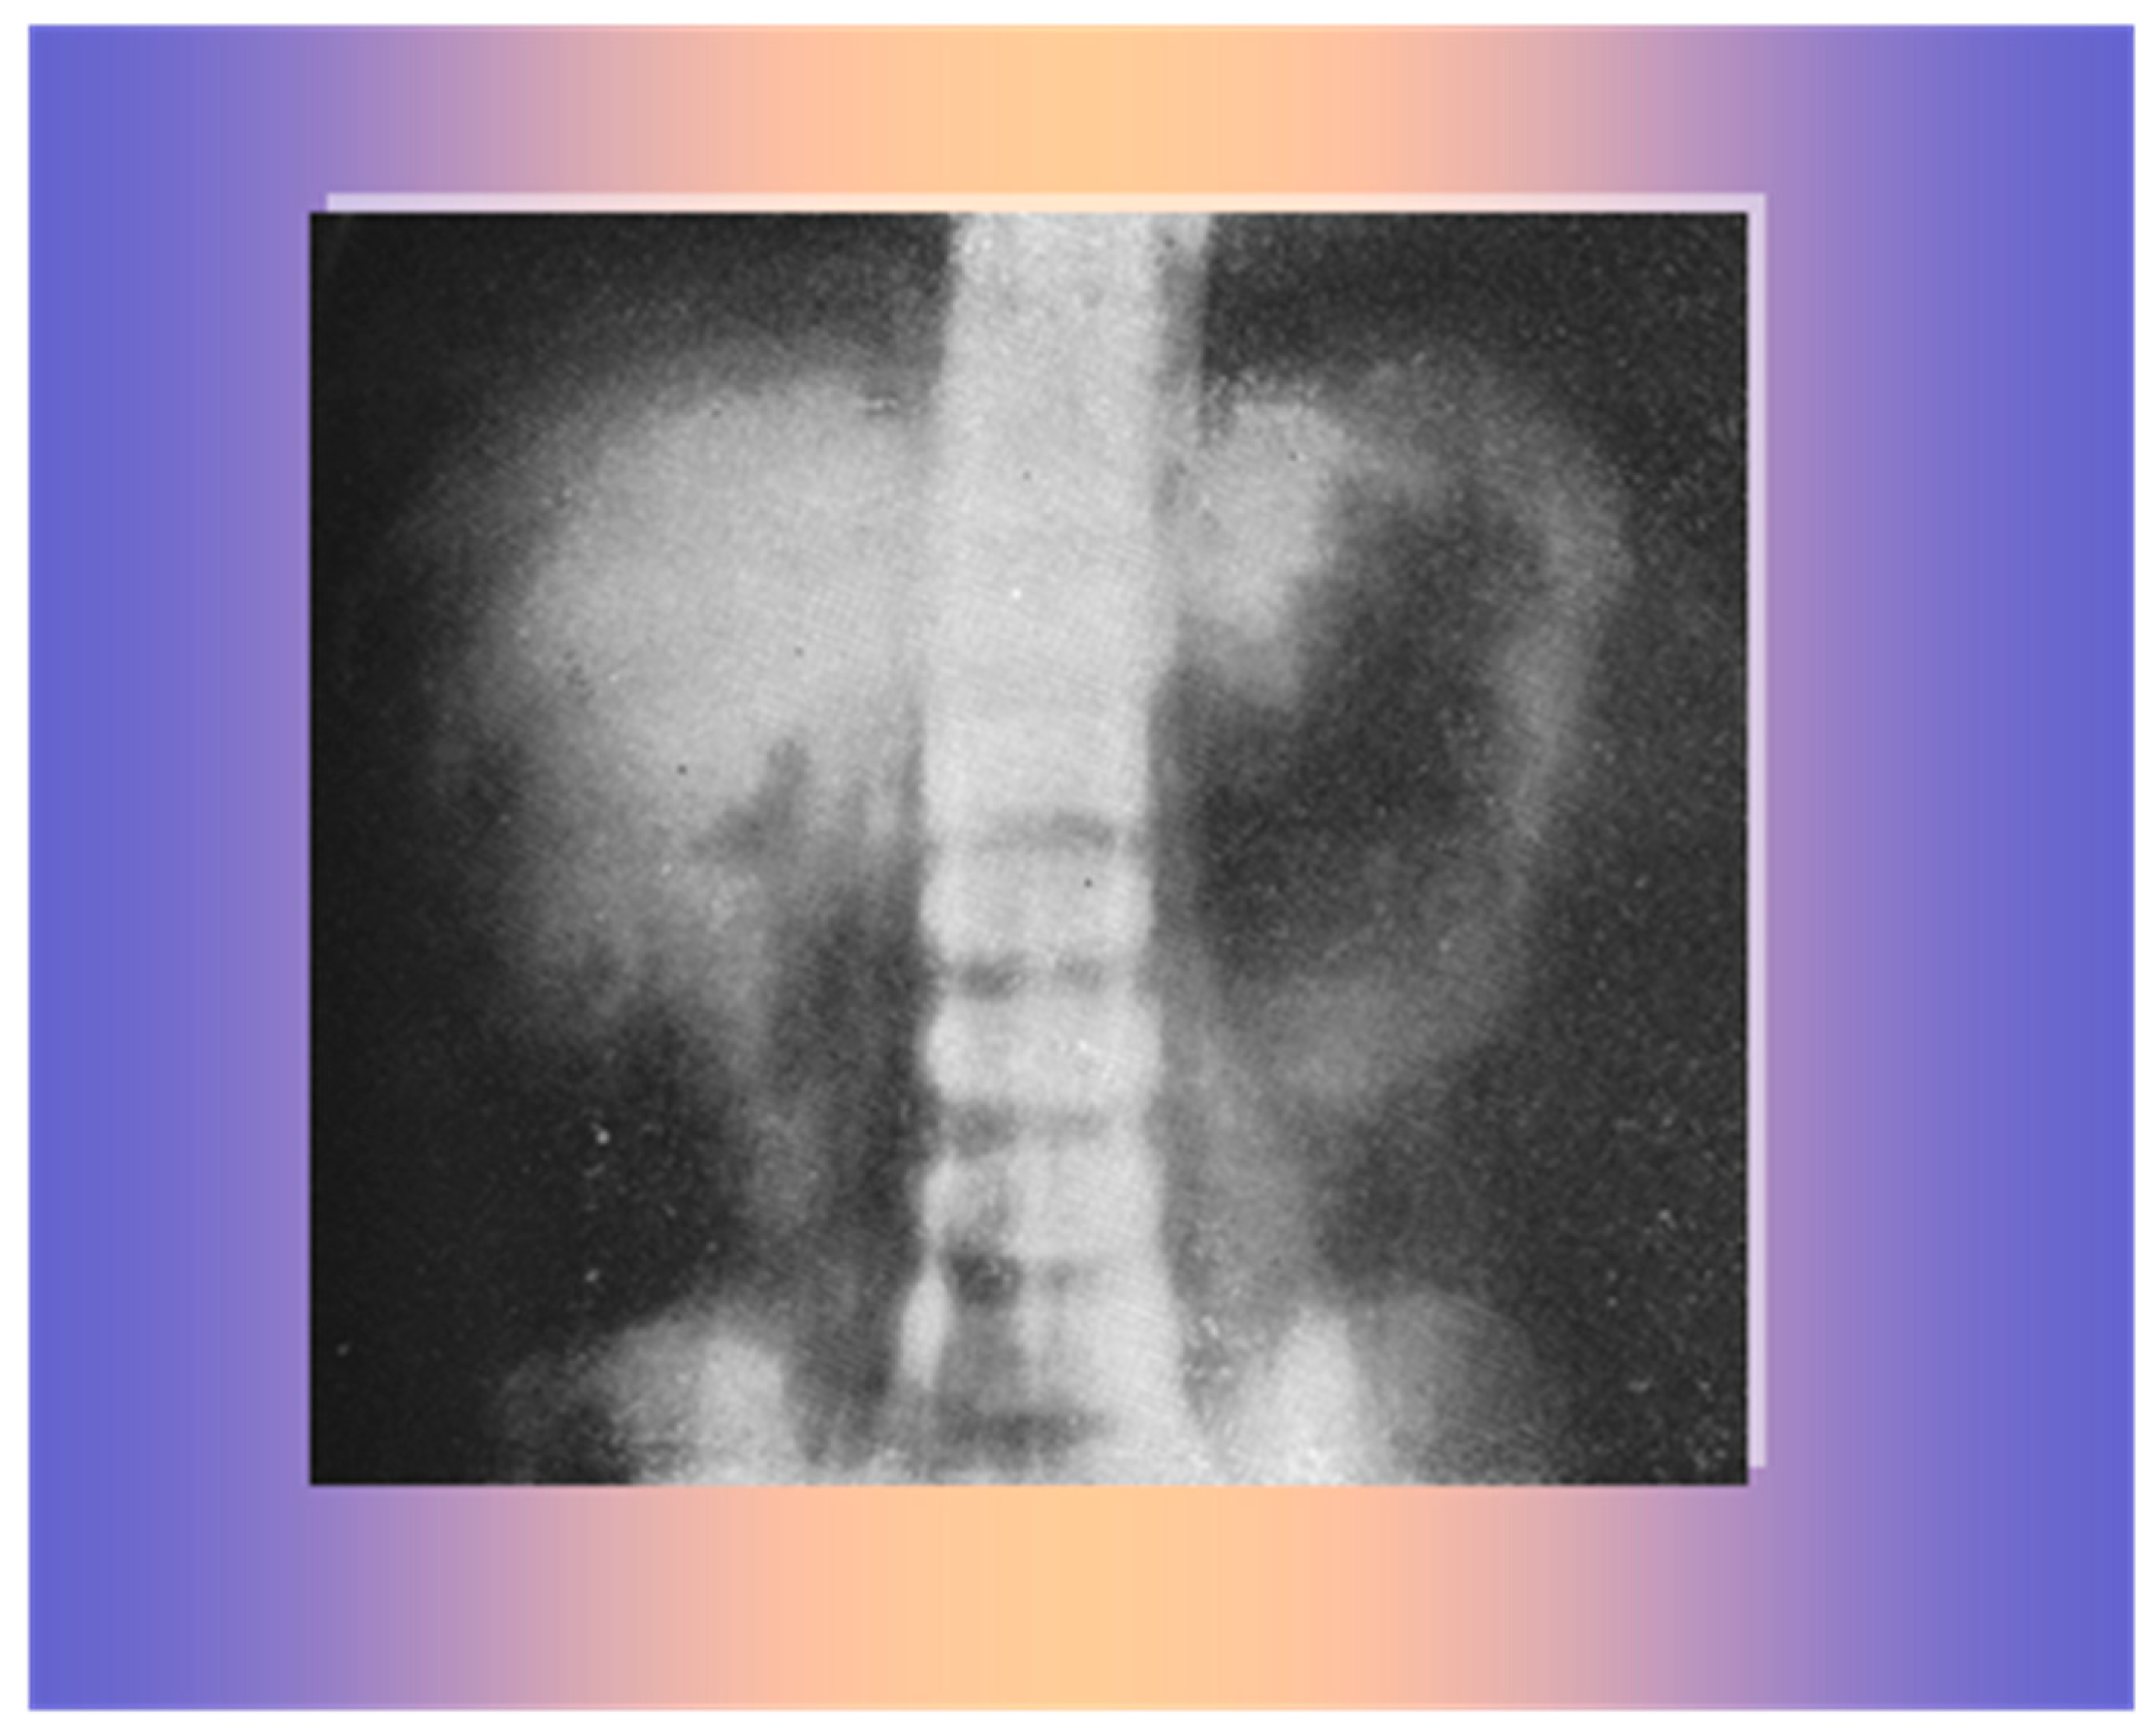

2. Case 1

3. Case 2